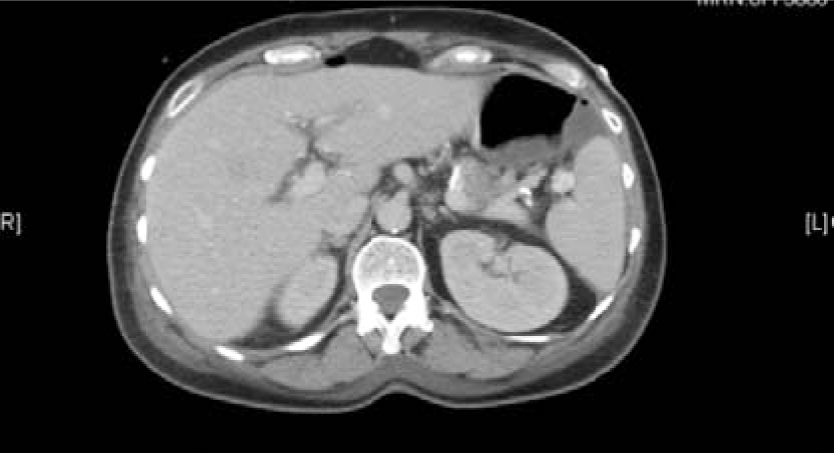

A 55-year-old female with recurrent Stage IIIA ovarian cancer, initially low malignant potential tumor with micropapillary features which then progressed to low-grade serous carcinoma. Patient was originally diagnosed with ovarian cancer in January 2009, after experiencing abdominal pain, nausea and vomiting. Since then, patient has had a complicated medical course with multiple hospitalizations throughout the years. Initial imaging revealed bilateral adnexal masses, omental lesion and ascites (Figure 4 and 5). A therapeutic and diagnostic paracentesis was performed and ascites fluid was positive for papillary serous ovarian tumor. A primary debulking surgery including a total abdominal hysterectomy with bilateral salpingo-oophorectomy, omentectomy, bilateral paraaortic and pelvic lymphadenectomy was performed. Initial pathology report revealed a 10cm tumor of the right ovary and a 15cm tumor of the left ovary, which were both positive for serous borderline tumor with micropapillary features. Small bowel implants and omentum were also positive for serous borderline tumor. Lymph nodes and appendix were negative. She was diagnosed with ovarian cancer with serous borderline tumor stage IIIA and completed six cycles of adjuvant chemotherapy with carboplatin and taxol.

Figure 4: CT scan abdomen and pelvis. Extensive splenic and liver implants.

Figure 5: CT scan abdomen and pelvis. Peritoneal implant medial to spleen measuring 24x26 mm.